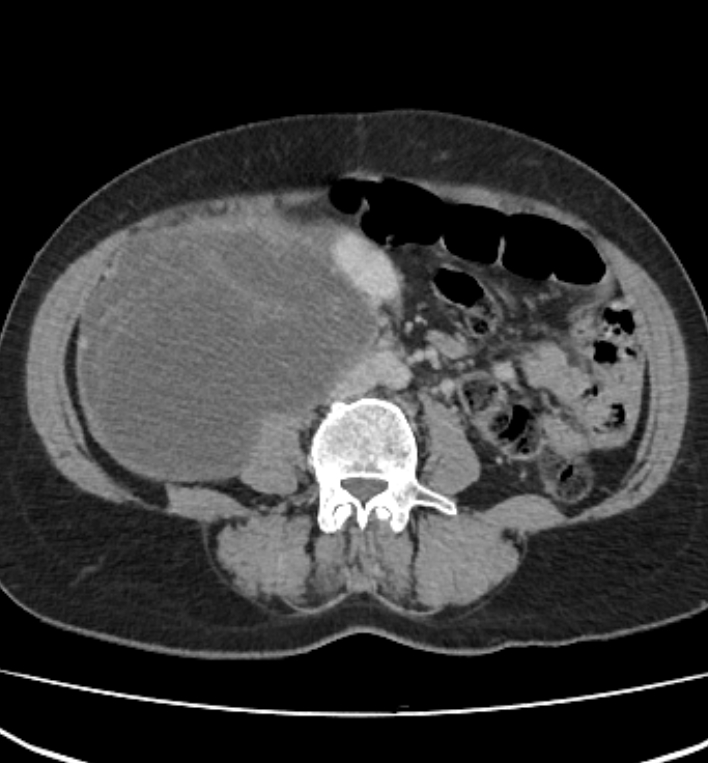

retroperitoneal rhabdomyosarcoma axial contrast

retroperitoneal rhabdomyosarcoma year contrast axial demonstrates bilateral extention